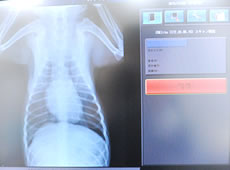

レントゲン検査 - 骨格や臓器の形状・状態の異常、骨折の有無などを確認します。